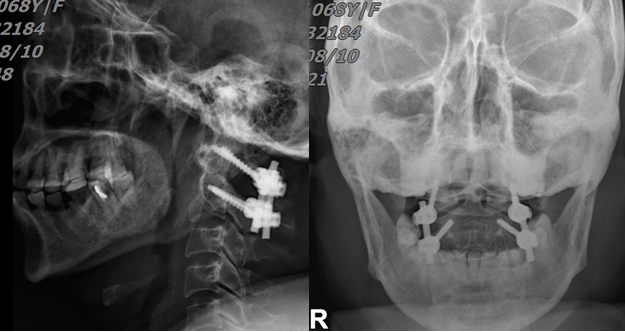

经过充分的术前沟通和准备,8月7日,陈志伸主任医师、王庆敏副主任医师及其手术团队依靠精湛的技术,历时2小时,成功为患者实施了“颈后路寰枢椎钉棒内固定+植骨融合术”。术后第1天患者可以在支具保护下坐起,术后3天可独立下地行走!

图三:术后复查:螺钉位置良好,骨折复位满意